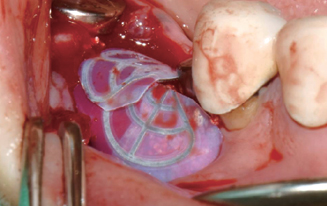

Wifi-Mesh 준비 및 다듬기

#45 & #46 골 결손 부위에

Wifi-Mesh 위치시킴